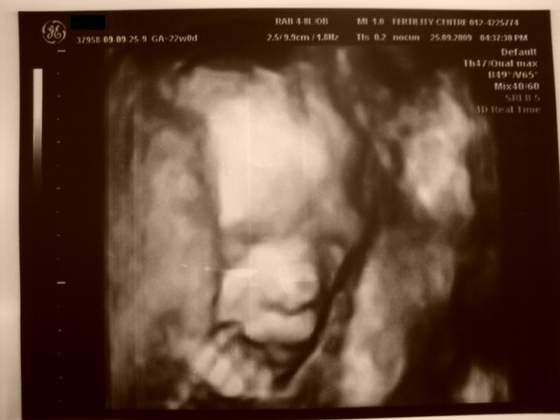

Zatem przedstawiamy naszego synka :-)